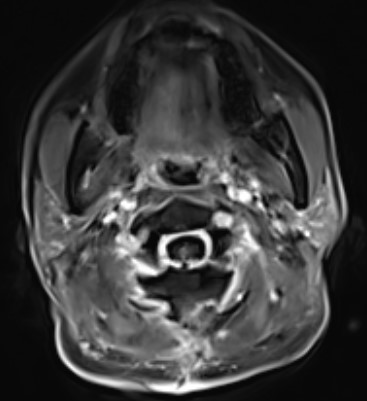

入院查头颈部MR提示C1到C2髓内占位,脊髓肿胀明显